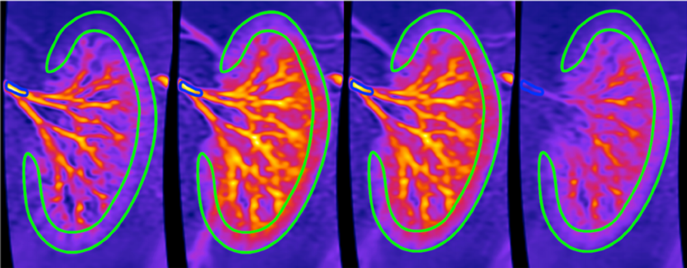

Among other topics, we have been focusing on hyperpolarizing water for MRI applications, targeting high-contrast perfusion (Figure 1) and angiographic imaging.

Figure 1: Renal angiography in a pig injected with water-based contrast agents at different time steps.8

However, hyperpolarizing water is far from trivial. This is mostly because of the paramagnetism of stable radicals used in the dDNP process to create the hyperpolarization: at the moment of injection they are the main source of signal, thus MR contrast, loss. Images in Figure 1 were recorded by perfusing a pig kidney with water polarized to 5% only. How beautiful would it be to record images using water hyperpolarized to its 100 % theoretical limit?